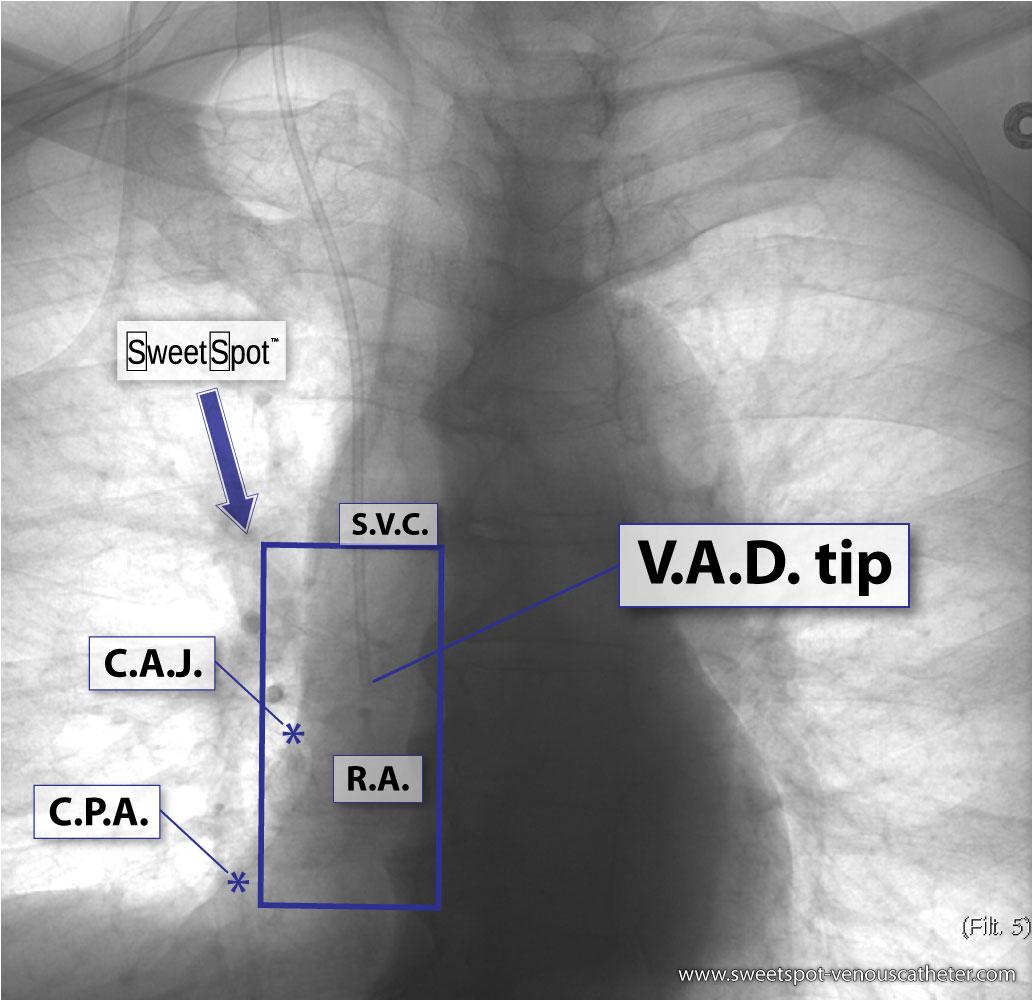

1. When I place a VAD under flouroscopic visualization, my optimal tip position is in the bottom of the box at expiration. See Fig.# 25 - Gallery.

2. On inspiration upright CXR, the tip of VAD is ideally at C.A.J. See Fig.# 09 - Gallery.

3. Chest x-ray rotation tissues: Not infrequently, the chest x-ray will be rotated causing the right cardiac margin to deviate from its normal AP appearance. In such situations, depending on the degree of rotation, an estimation of the SWEET SPOT™ is all that may be possible. In such circumstances, the right cardiophrenic angle is the most reliable anatomic landmark. Since the right atrium is immediately cephalad to a normally positioned right cardiophrenic angle, a reliable estimation of acceptable catheter tip location is still possible. The height, and consequently the width of the rectangular Sweet Spot™ box will be less exact and therefore a relatively short catheter tip position may require a non- rotated chest x-ray to confirm an acceptable location. Aim for the right atrium. See Figs. T.1, T.2, and T.3.

8. Even on normal frontal chest x-rays, there can be significant variation in the appearance of the cardiomediastinal silhouette which can result in slight subjectivity in the exact location of the margins of the SWEET SPOT™. The closer the catheter tip is to the cavoatrial junction, the less this matters.